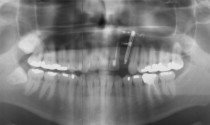

Implantate werden als Ersatz der Zahnwurzel eingesetzt um daran Einzelkronen, Brücken oder Prothesen zu befestigen! Wir verwenden hierfür 3 verschiedene Implantatsysteme und führen auch erforderlichenfalls Knochenaufbau durch.

Zur Befestigung von Totalprothesen bieten wir auch ein minimalinvasives Implantat-System an.